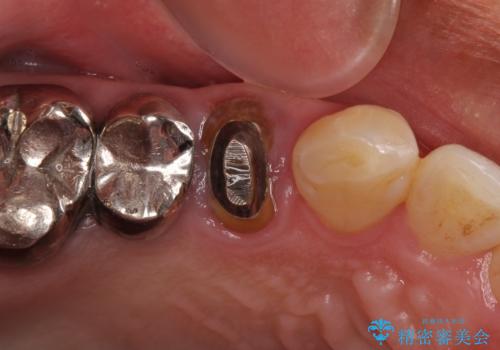

- 奥歯に違和感を感じており、抜歯の必要性を感じて来院された患者様です。

診査の結果、5本の奥歯を抜歯してインプラントによる補綴治療が必要と診断されました。